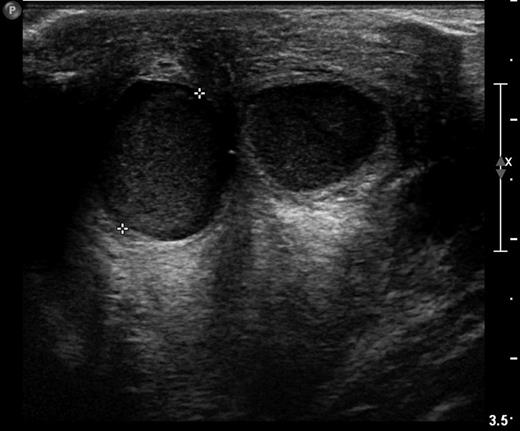

A healthy 15-year-old girl presented to her GP with mastalgia and periareolar cellulitis of her right breast. She was initially treated with a course of oral flucloxacillin but after 2 days there was no improvement and an emergency hospital referral was organized. Physical examination identified periareolar erythema in the presence of a tender subareolar inflammatory mass and a mild pyrexia. A provisional diagnosis of retroareolar abscess was made and an ultrasound scan (USS) was requested. The USS revealed three focal fluid collections or cysts located behind the nipple which were in direct communication with each other. The cysts contained echogenic fluid with surrounding hyperaemia and subcutaneous oedema. After conversation with a consultant breast surgeon, it was decided not to aspirate the mass but to discharge the patient on an additional course of amoxicillin and follow her up 3 days later with consultant review.

Subsequent review revealed a mild improvement in symptoms and an alternative diagnosis of retroareolar cyst established. Follow-up with repeat USS 2 days later revealed a well-defined anechoic lesion cystic in nature rather than abscess. The lesion had decreased in size, and clinical examination revealed no existing erythema and decreased tenderness on palpation of the inflammatory mass.

Sonography is the radiological modality that best characterizes retroareolar cysts [1, 4–6]. Garcia et al. [4] in a review of USS in the adolescent breast describe asymptomatic retroareolar cysts presenting as anechoic masses in the breast tissue. The cysts can be multiple in number, round or lobular in shape and contain internal septations or isolated echoes (Fig. 1; [4, 5]). Garcia et al. [4] further describe inflammatory retroareolar cysts to contain echogenic debris, fluid filled levels, internal septations and increased peripheral vascularity [4]. This correlates with our sonographic findings (Fig. 2) and Huneeus et al.'s [1] series who noted the enhanced vascularity only in the symptomatic cyst [1]. Interestingly, Huneeus et al. [1] also reported the presence of bilateral asymptomatic cysts in almost half of their patients.